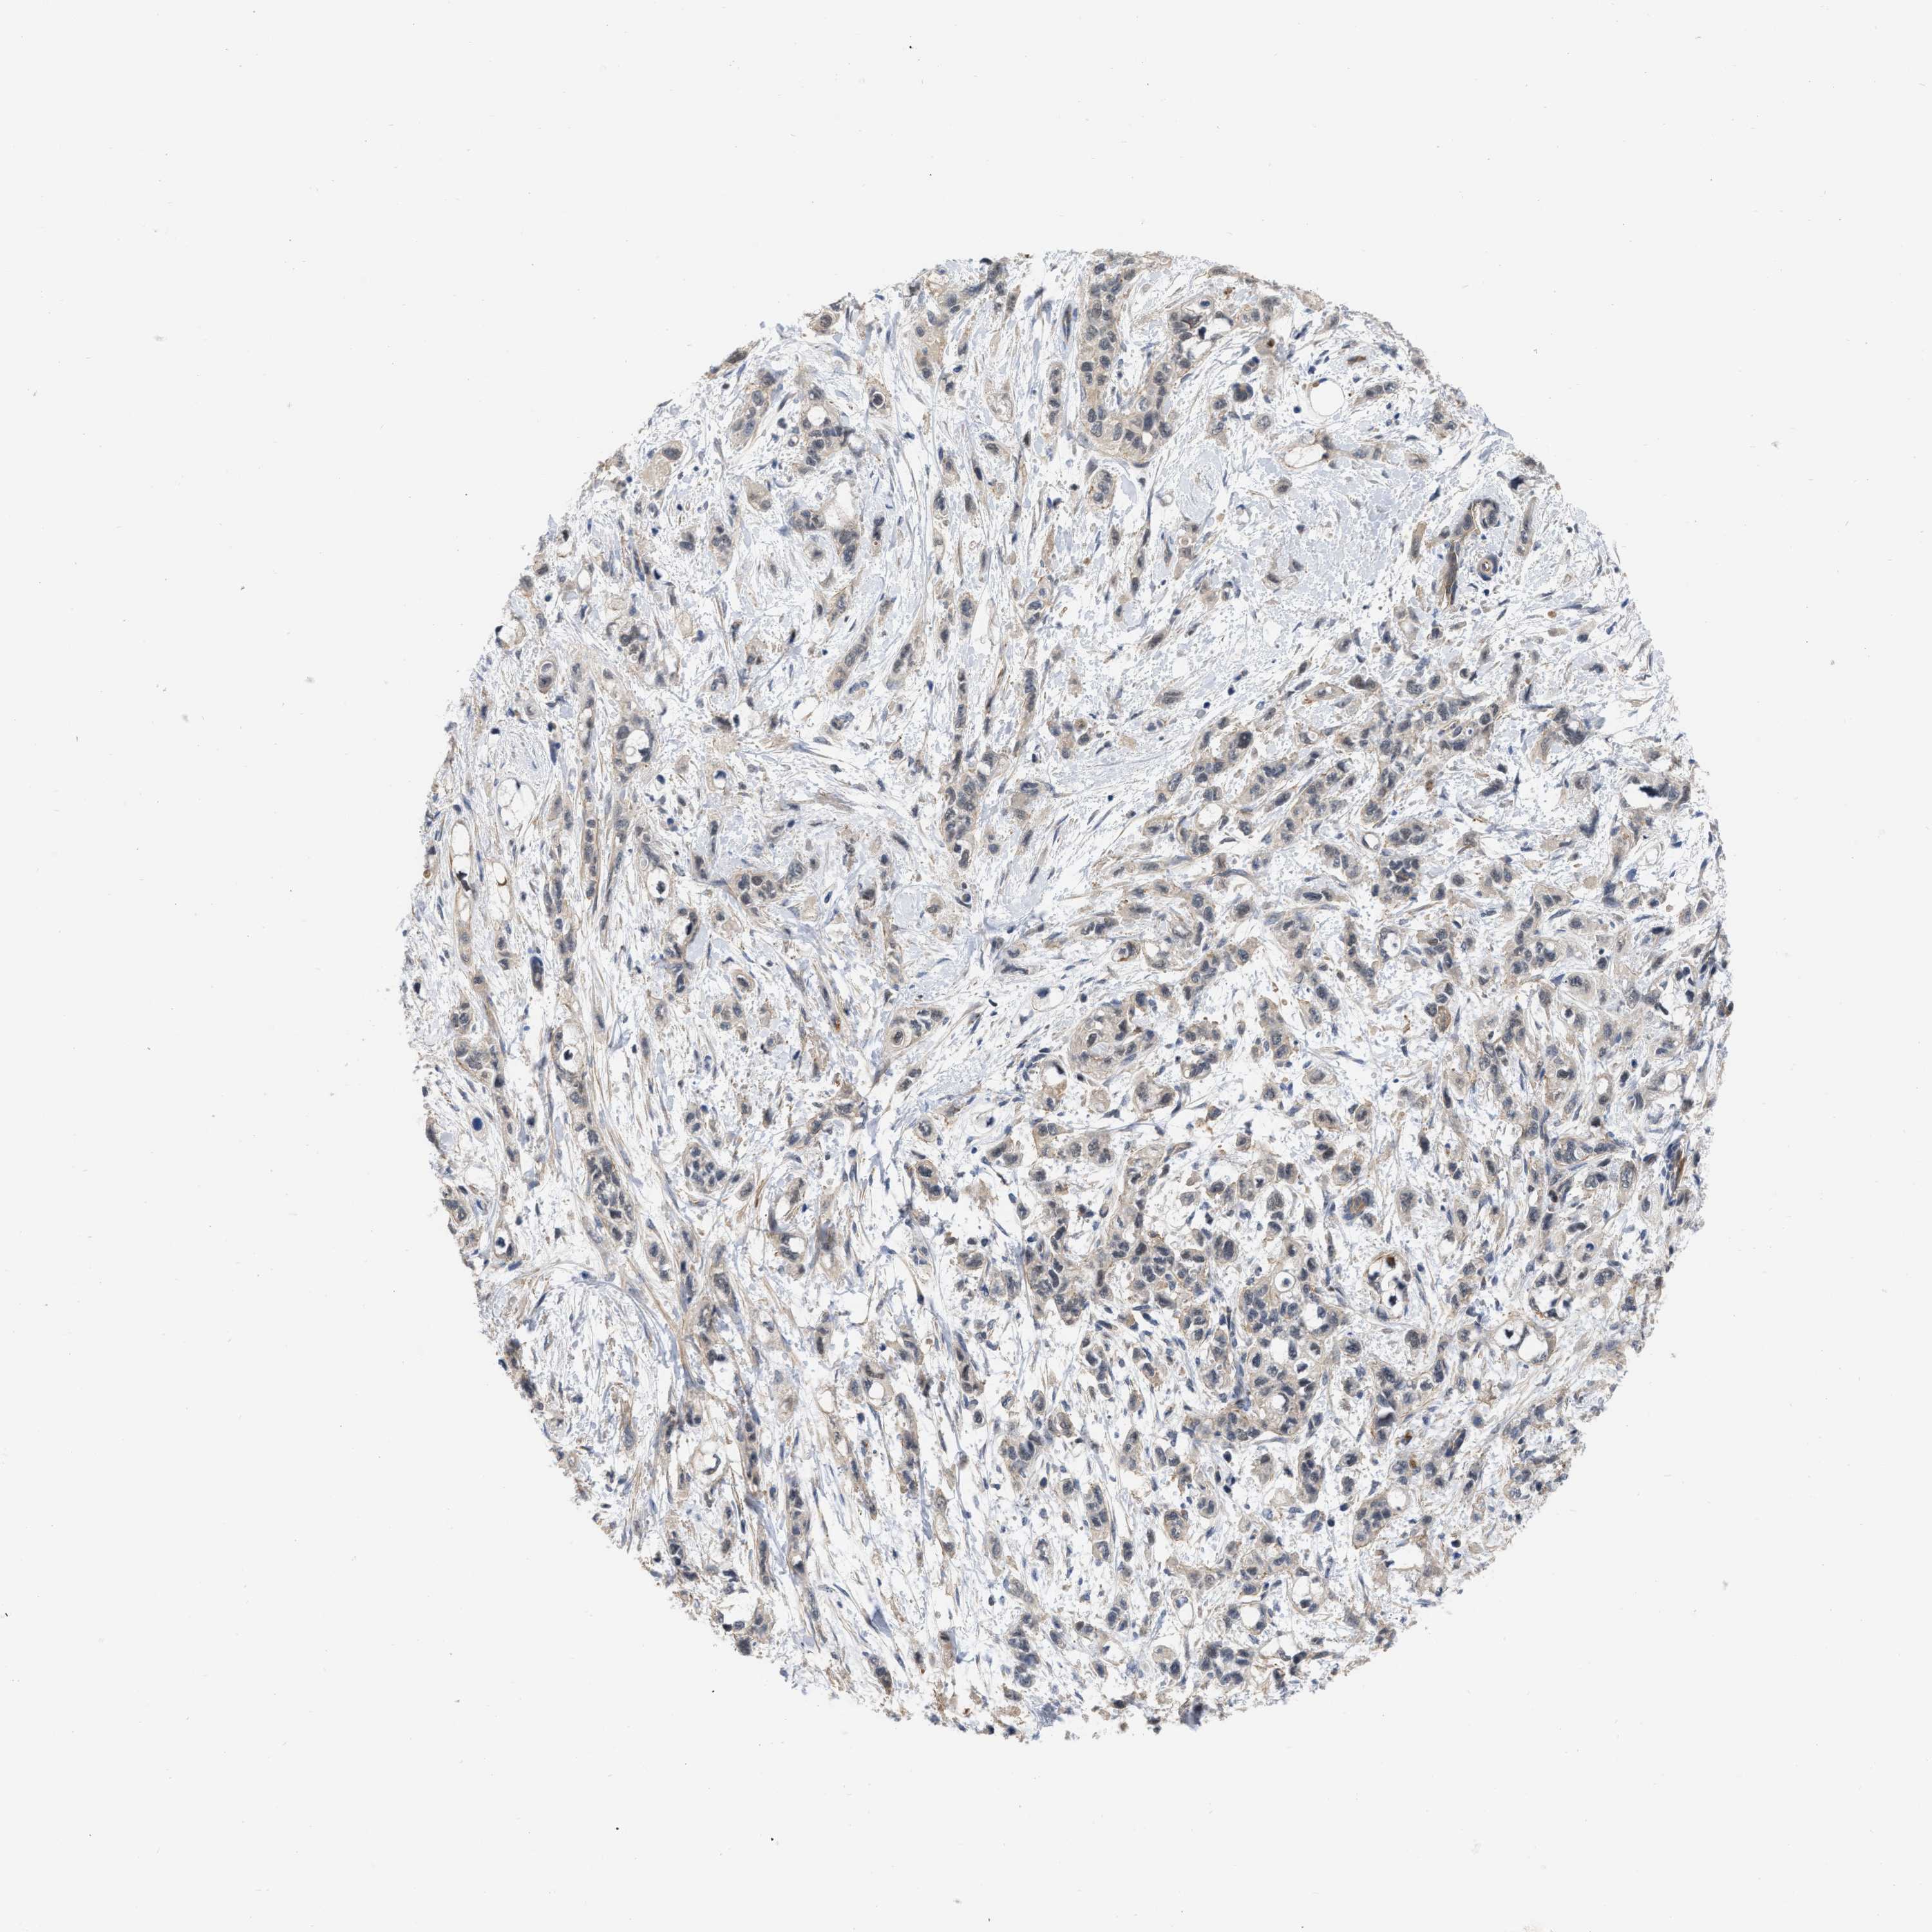

PANCREATIC CANCER - Protein expressioni

A mouse-over function shows sample information and annotation data. Click on an image to view it in a full screen mode. Samples can be filtered based on level of antibody staining by selecting one or several of the following categories: high, medium, low and not detected. The assay and annotation is described here.

Note that samples used for immunohistochemistry by the Human Protein Atlas do not correspond to samples in the TCGA dataset.

Antibody stainingi

Antibody staining in the annotated cell types in the current human tissue is reported as not detected, low, medium, or high, based on conventional immunohistochemistry profiling in selected tissues. This score is based on the combination of the staining intensity and fraction of stained cells.

Each image is clickable and will lead to virtual microscopy that enables deeper exploration of all samples and also displays staining intensity scores, fraction scores and subcellular localization as well as patient and tissue information for each sample.

Antibody HPA019832

Antibody HPA024338

Staining

High

Medium

Low

Not detected

Intensity

Strong

Moderate

Weak

Negative

Quantity

>75%

75%-25%

<25%

None

Location

Nuclear

Cytoplasmic/membranous

Cytoplasmic/membranous,nuclear

Adenocarcinoma, NOS